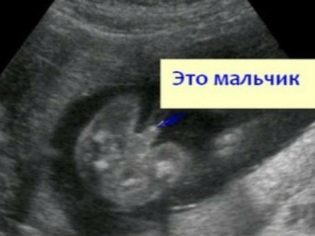

На данном сроке узист также может определить пол будущего ребенка, и вероятность ошибки в этом случае крайне мала.

Уже на 19-й неделе беременности можно узнать, будет ли у вас мальчик или девочка. Это связано с тем, что к этому сроку у плода уже сформированы основные внешние половые органы.